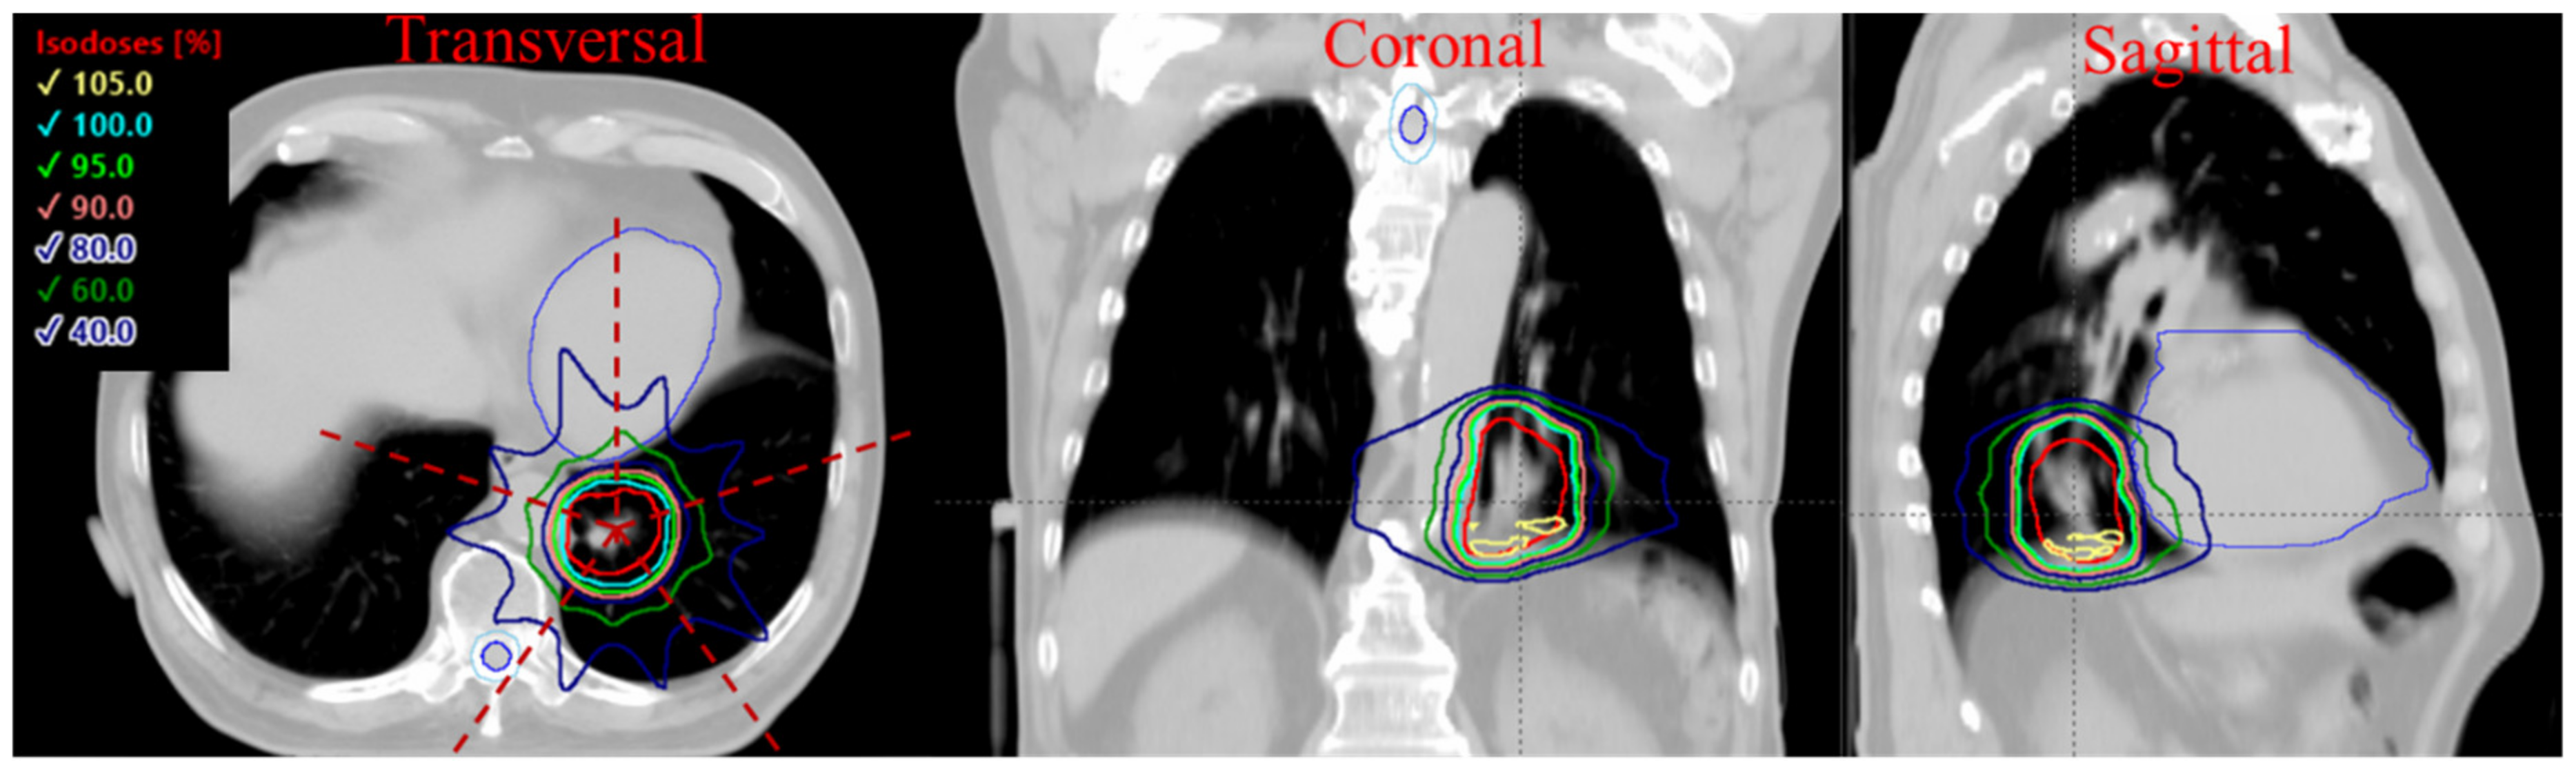

3.2. Plan Quality Assessment

3.3. 3D Dose Rate